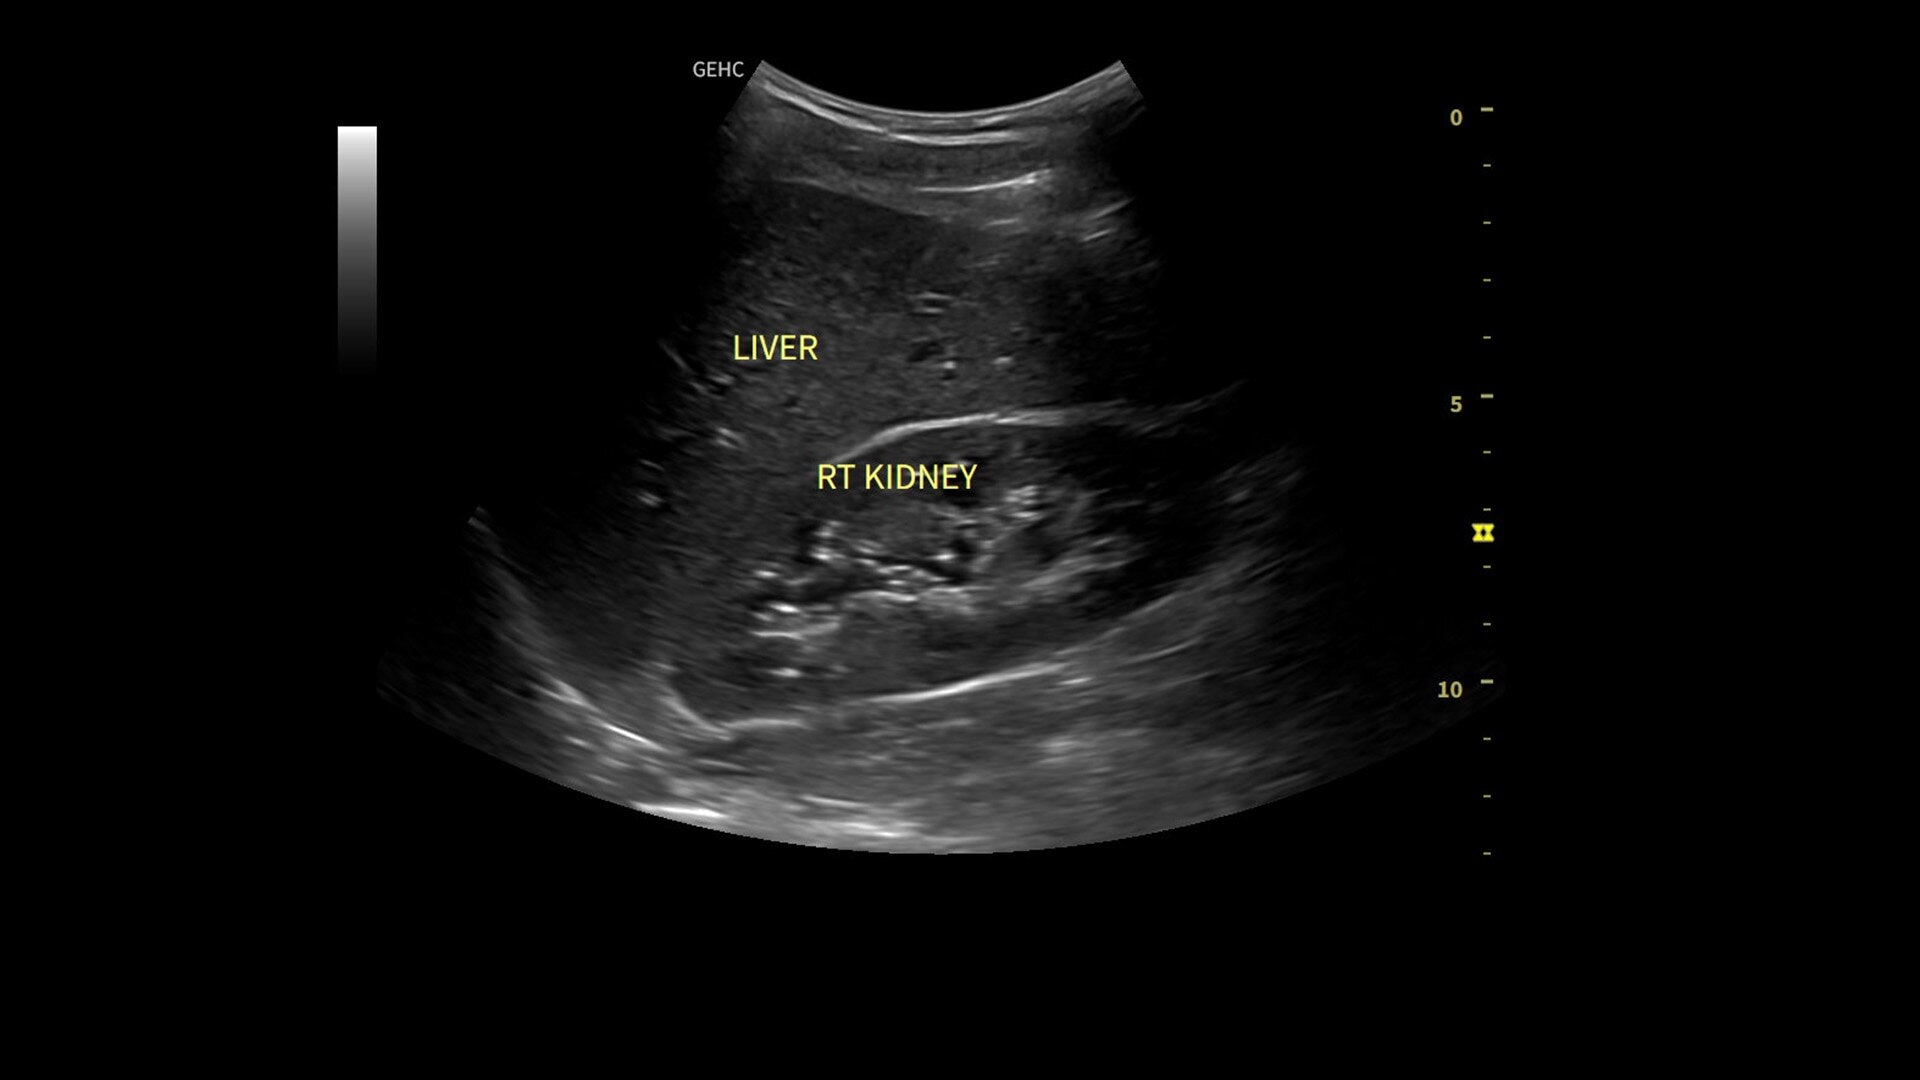

Whizz Label

AI-enabled labeling of the right kidney, gallbladder and liver

• Use automated labeling in the RUQ with Whizz Label